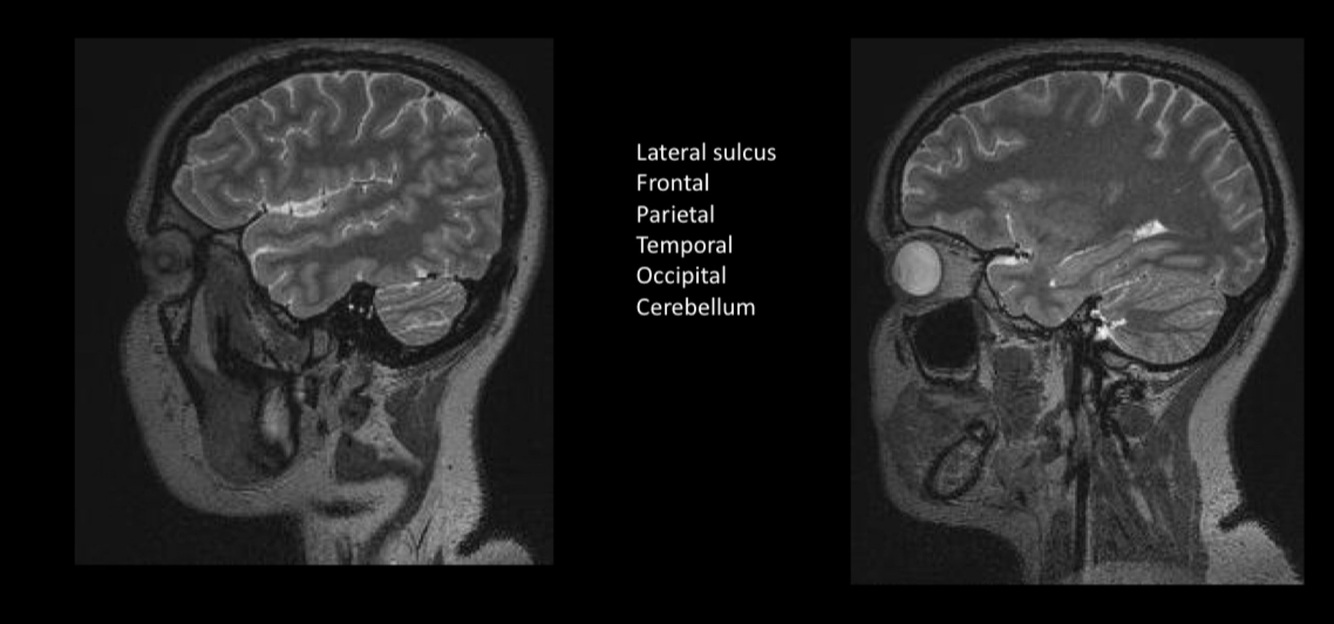

In this image we can see the…

Sylvian sulcus